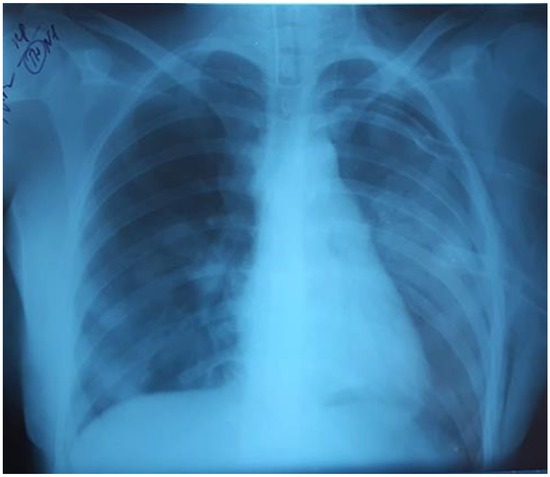

Severe Coronavirus HCoV-NL63 Pneumonia in a Patient Receiving Blinatumomab with Secondary Antibody Deficiency in COVID-19 Times

by Claudia C. Paredes-Amaya, Lorena Matta-Cortes and Andrés Felipe Zea-Vera

Introduction: Human coronavirus NL63 (HCoV-NL63) is one of four common human respiratory coronaviruses. It causes lower respiratory tract infections in young children, elderly and immunosuppressed people, which could result in fatal outcomes. In this time of pandemic, we want to highlight the importance of other coronaviruses infection besides SARS-CoV-2, especially in a patient with underlying conditions like acute lymphoblastic leukemia, receiving immunosuppressive therapy that could result in humoral secondary immunodeficiencies. Case report: We present the case of a 44-year-old Colombian man with acute lymphoblastic leukemia who developed HCoV-NL63 pulmonary infection after the first month of treatment with blinatumomab complicated with severe secondary hypogammaglobulinemia. HCoV-NL63 was detected by multiplex PCR, and HCoV-NL63 viral pneumonia was diagnosed. Hypogammaglobulinemia was studied by determining serum immunoglobulins levels and protein electrophoresis. The treatment consisted of supportive therapy and replacement with intravenous immunoglobulins. After therapy, the patient improved his oxygenation, and the infection was resolved in a few days. Conclusions: This case highlights the relevance of other coronaviruses infections besides SARS-CoV-2 in patients receiving immunosuppressive therapy who develop secondary antibody deficiency, and the importance of replacement therapy with intravenous immunoglobulins at early stage of infection with HCoV-NL63. Full article

Show Figures